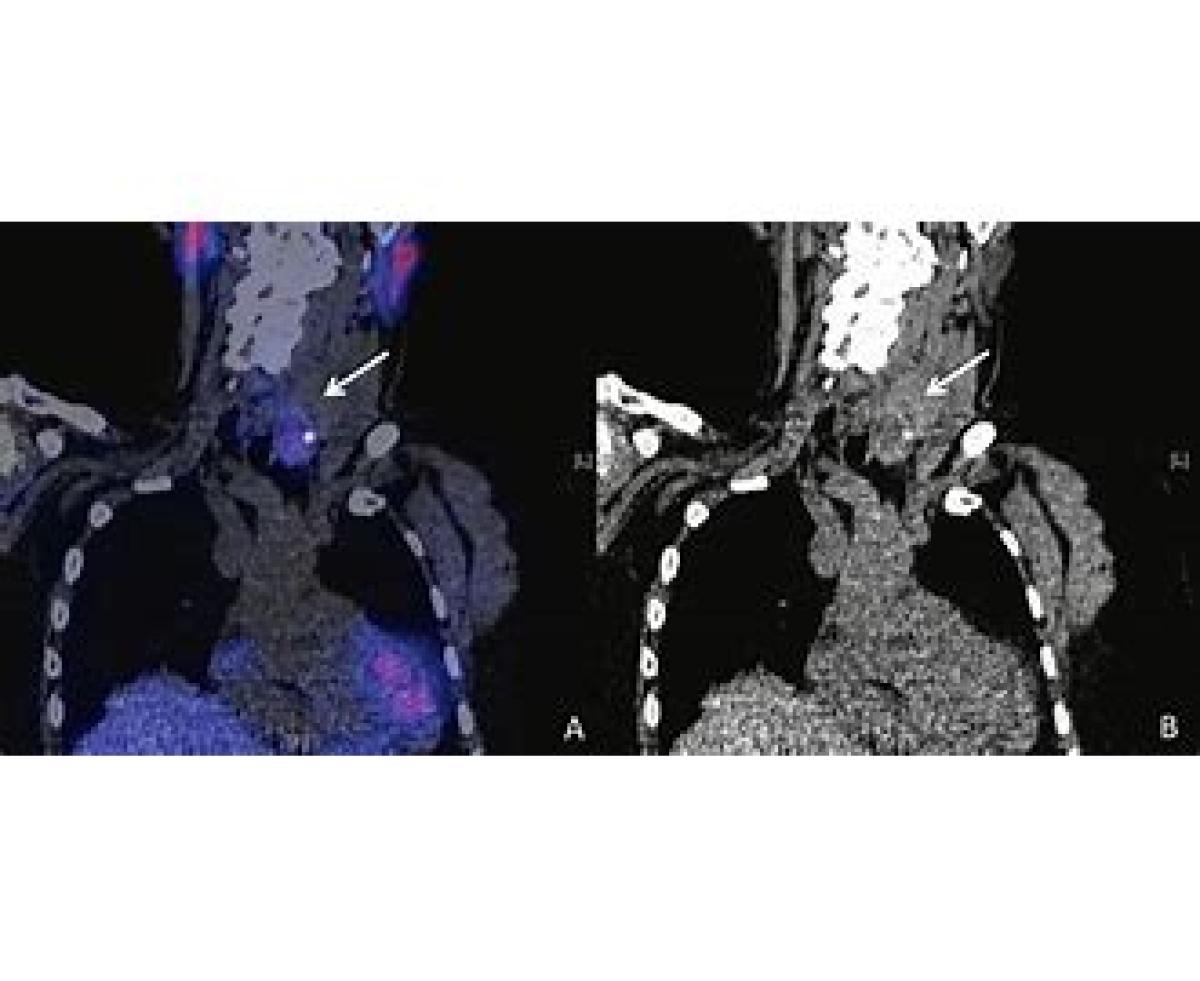

اسکن سستامیبی تکنیتیوم-۹۹ام (به انگلیسی: Technetium-99m Sestamibi scan) که گاهی به اختصار مخفف MIBI scan شناخته می‌شود، نوعی آزمایش در پزشکی هسته‌ای است. این آزمایش‌ها بخصوص در معاینات قلبی کاربرد دارند.

نواحی سکته قلبی، مواد تزریق شده فوق را جذب می‌کنند. همانند سینتیگرافی تالیم-۲۰۱، می‌توان از این ماده در آزمایش قلبی موسوم به exercise tolerance test استفاده نمود که کمک می‌کند نواحی خونی کم‌جریان به ماهیچه‌های قلبی مشخص شود.